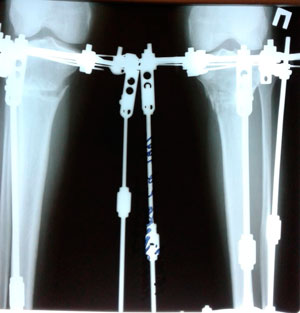

Исходник - 27 лет. Якутия.

Дата операции - 12.07.2019г.

Срок сращения - 95 дней.